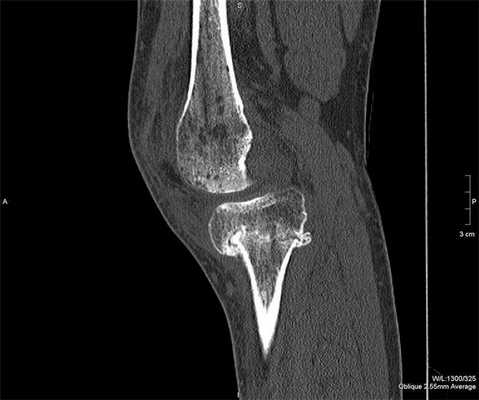

Из-за физики получения изображения кость лучше всего визуализируется на компьютерном томографе, а вот мягкие ткани и хрящевые образования лучше смотреть с помощью магнитно-резонансного аппарата.

КТ - это сокращение от компьютерной томографии. Это исследование проводится с помощью рентгеновских лучей и в результате сопровождается облучением пациента до 10 мЗв за одно сканирование. Компьютерное обследование гораздо информативнее обычной рентгенографии. Рентген дает врачам двухмерное изображение, а при компьютерной диагностике производится череда рентгеновских снимков. Они выполняются в разных проекциях, накладываются друг на друга, и в итоге рентгенолог получает реконструированное трёхмерное изображение коленной области.

На компьютерной томографии лучше, чем на МРТ, диагностируются:

- трабекулярные переломы;

- косточки внутри сустава (внутрисуставная мышь);

- микротрещины в костях;

- костные наросты и опухоли;

- суставные вывихи.

Компьютерная томография, в отличие от других диагностических методов, позволяет получать послойные изображения коленного сустава сразу в трех плоскостях, а проведенная при помощи современного программного обеспечения и с получением 3D-реконструкции, дает объемное представление о данной анатомической зоне.

Лучше всего на КТ-снимках видны именно кости. Это объясняется их высокой способностью поглощать рентгеновские лучи. Мягкие ткани, хрящевые образования визуализируются менее отчетливо, в этом КТ коленного сустава уступает по информативности МРТ.

Наиболее информативна компьютерная томография коленного сустава при свежих травматических повреждениях. На полученных снимках отчетливо видны кровоизлияния, гематомы мягких тканей, сложные для диагностики переломы. В случае опухолевого процесса хорошо определяются его границы, размеры, степень прорастания в окружающие ткани.